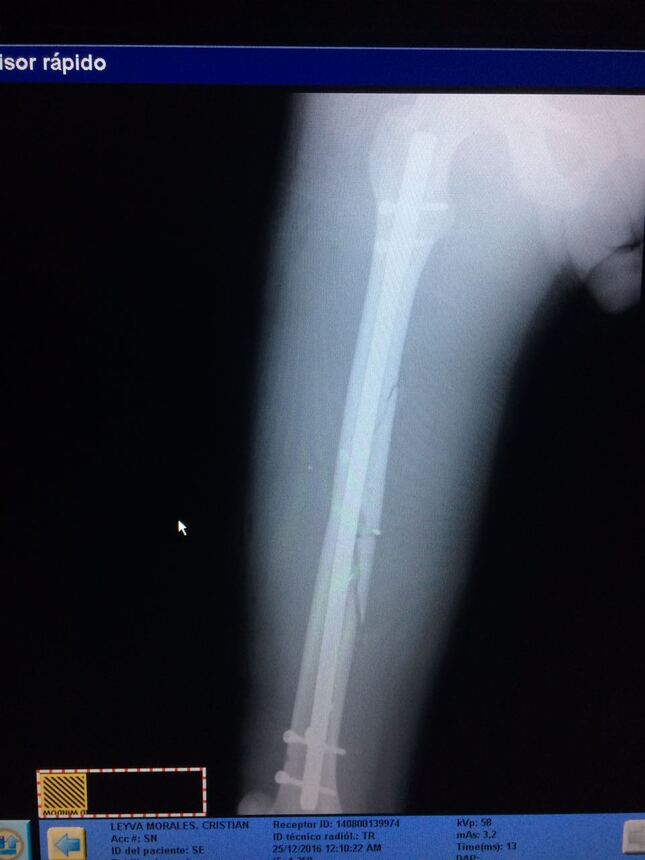

Clavo de fémur